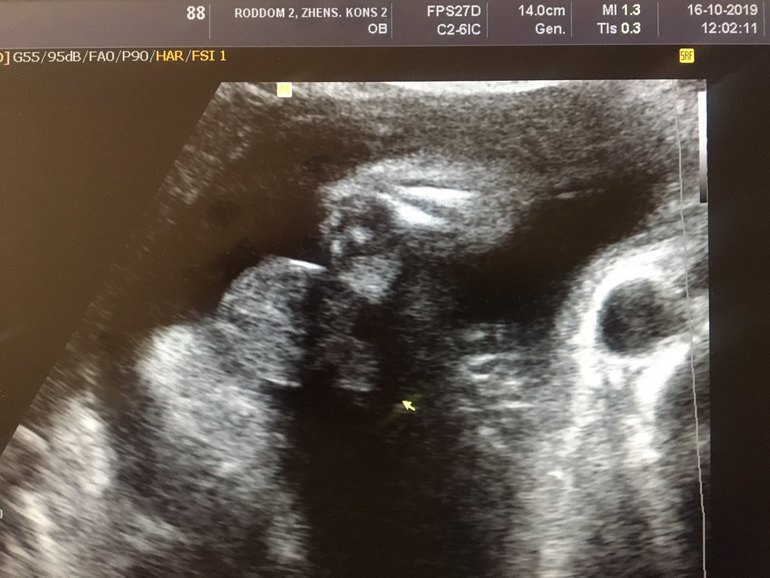

Пошли сегодня с мужем на узи.У нас будет мальчик😁А шли подтвердить ДЕВОЧКУ)